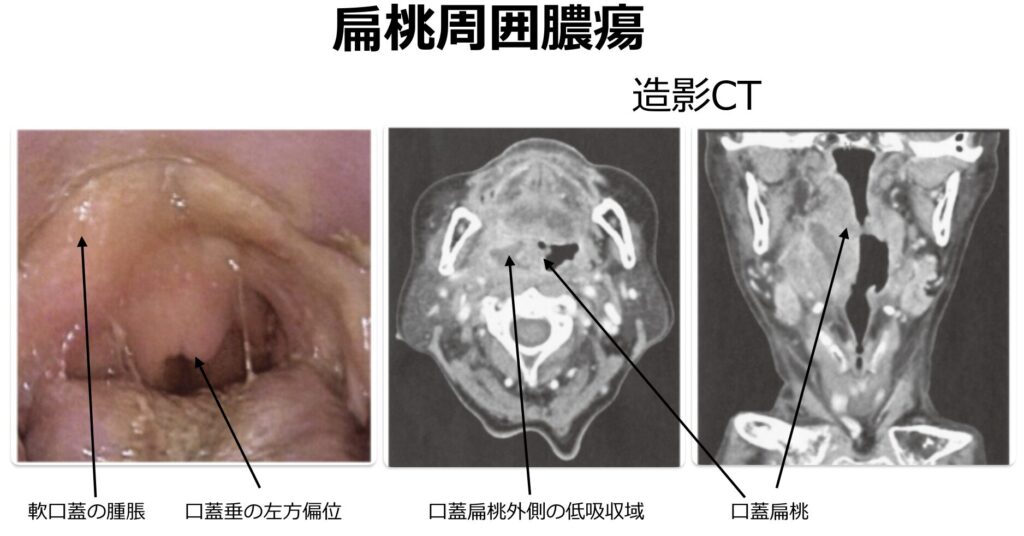

画像

- 扁桃周囲炎と扁桃周囲膿瘍の鑑別が視診上困難な場合や、傍咽頭間隙をはじめとする深頸部への膿瘍進展(ガス産生性膿瘍など)を評価するうえで、造影CTの施行が推奨されます

。あるいは、局所の最も膨隆している部位へ穿刺を行い、膿汁の吸引が確認できれば扁桃周囲膿瘍の確定診断となります